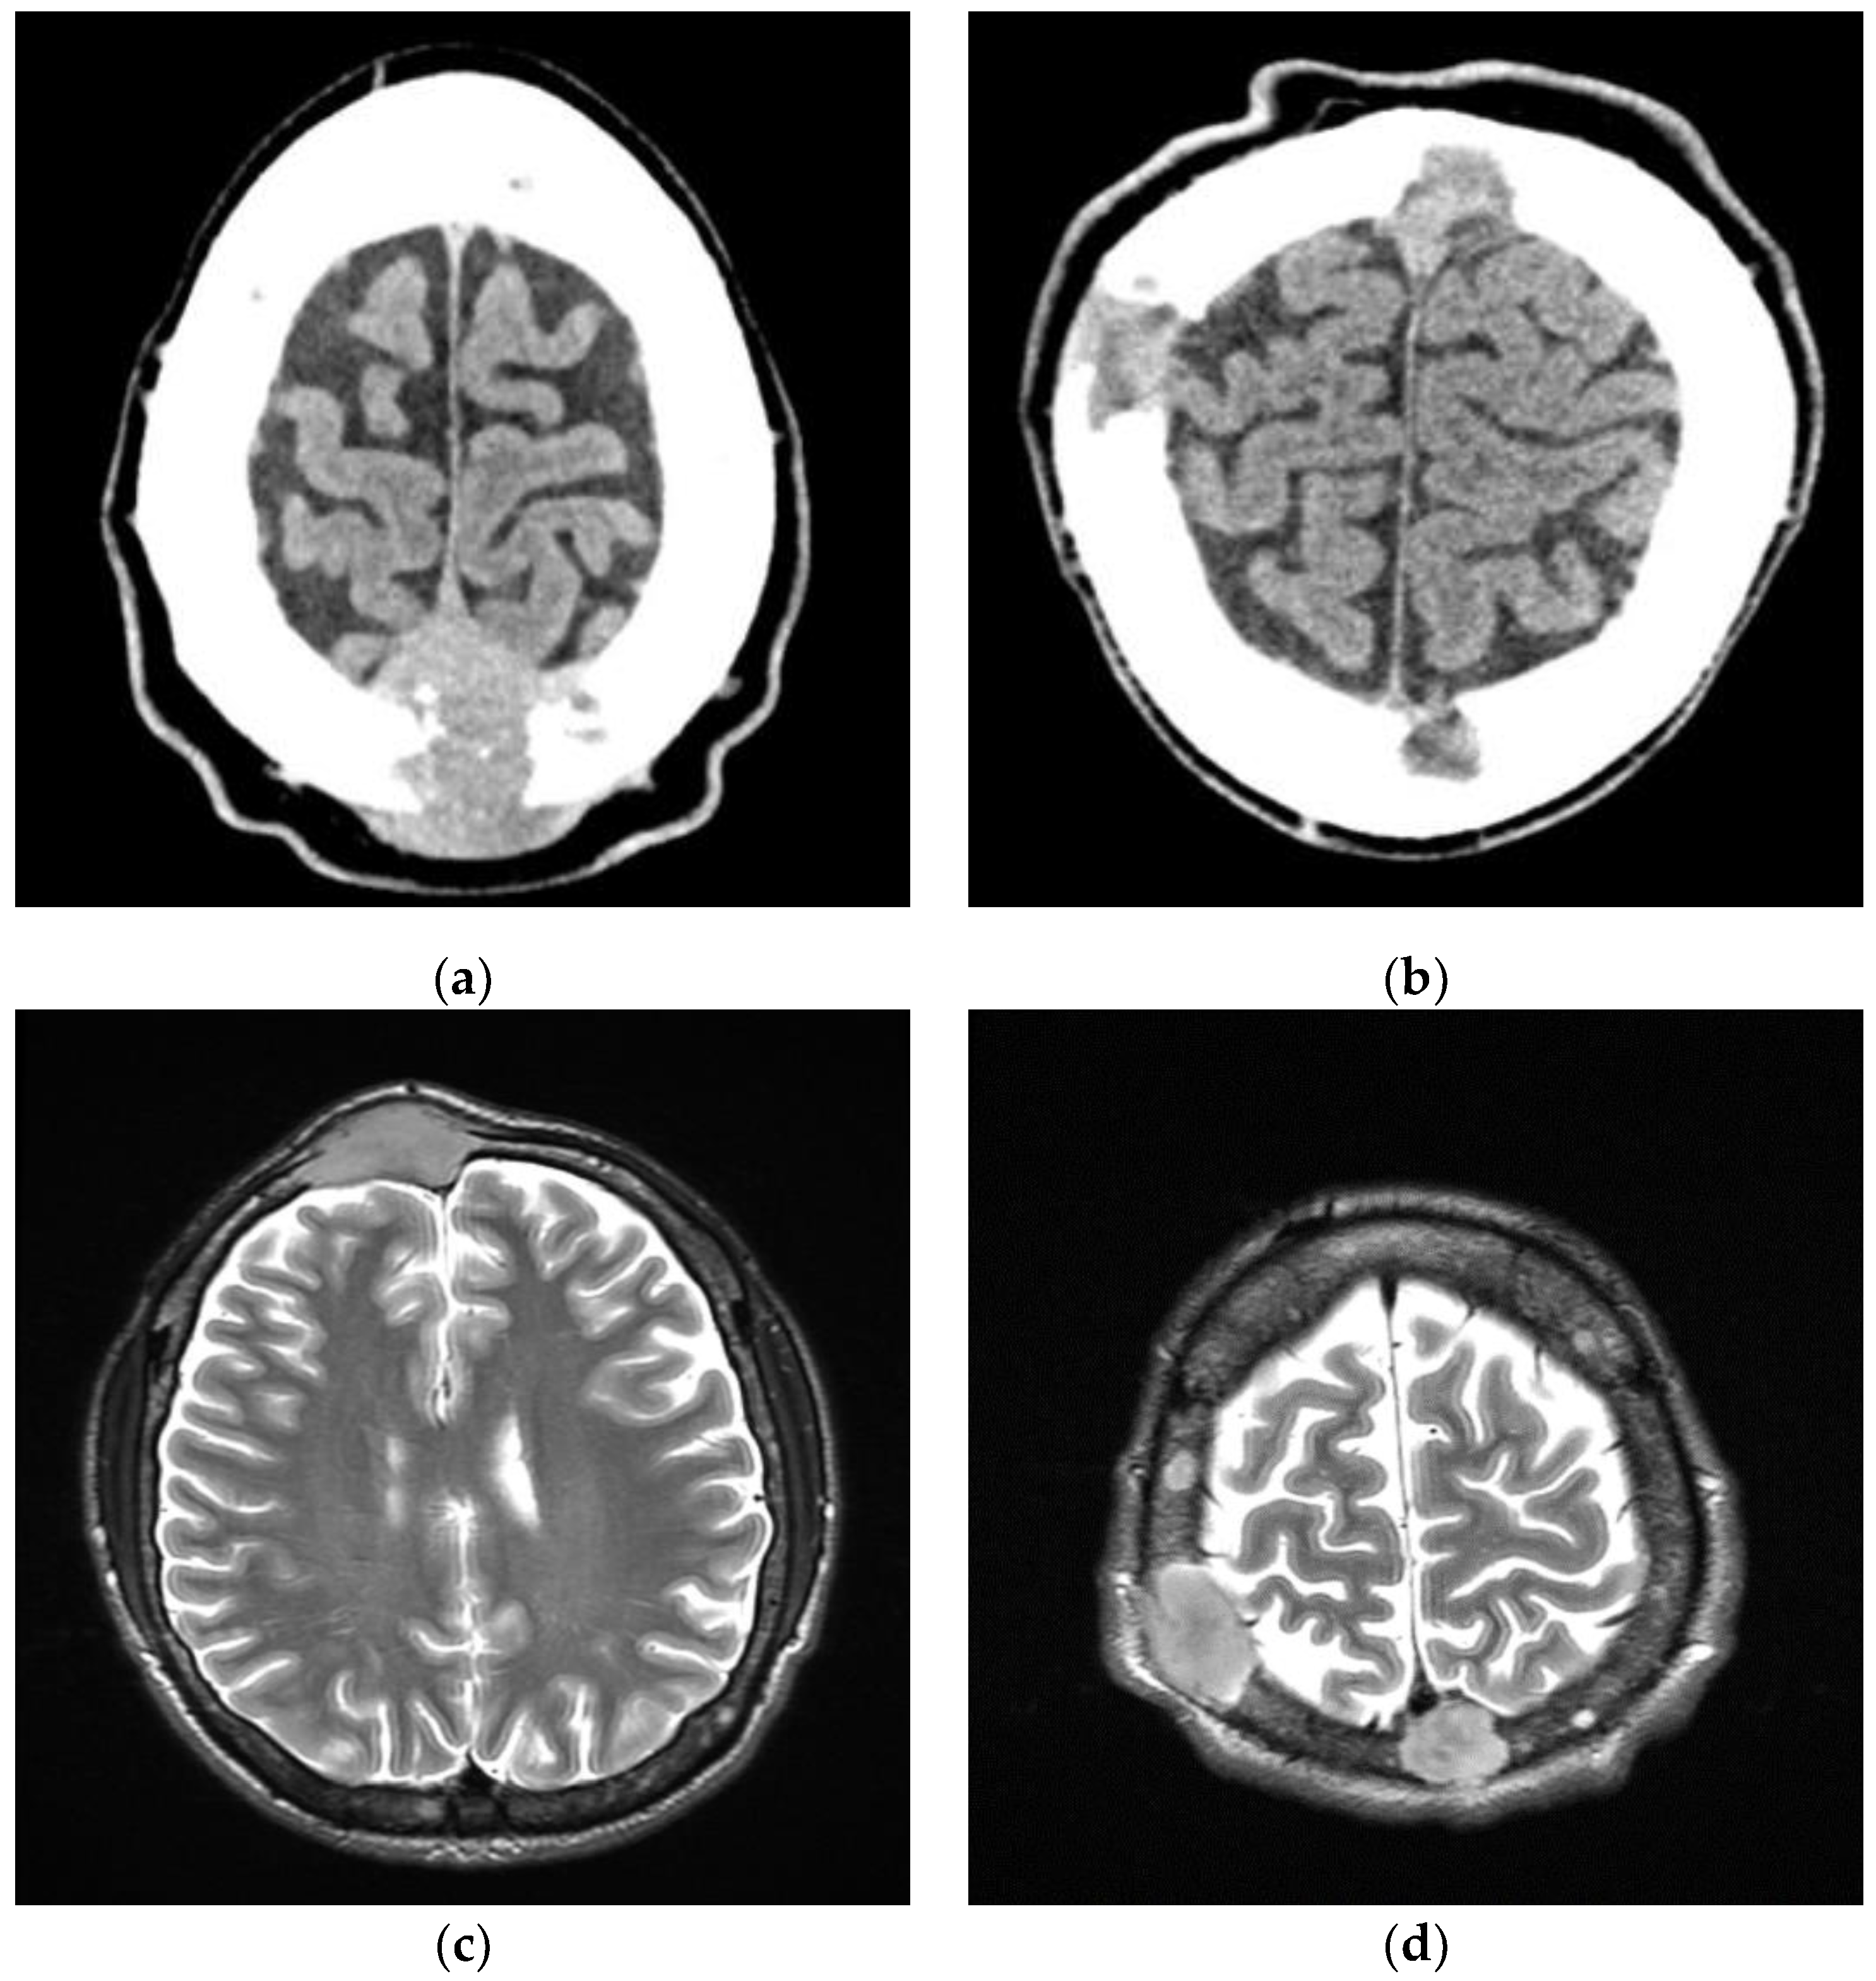

2. Case Report